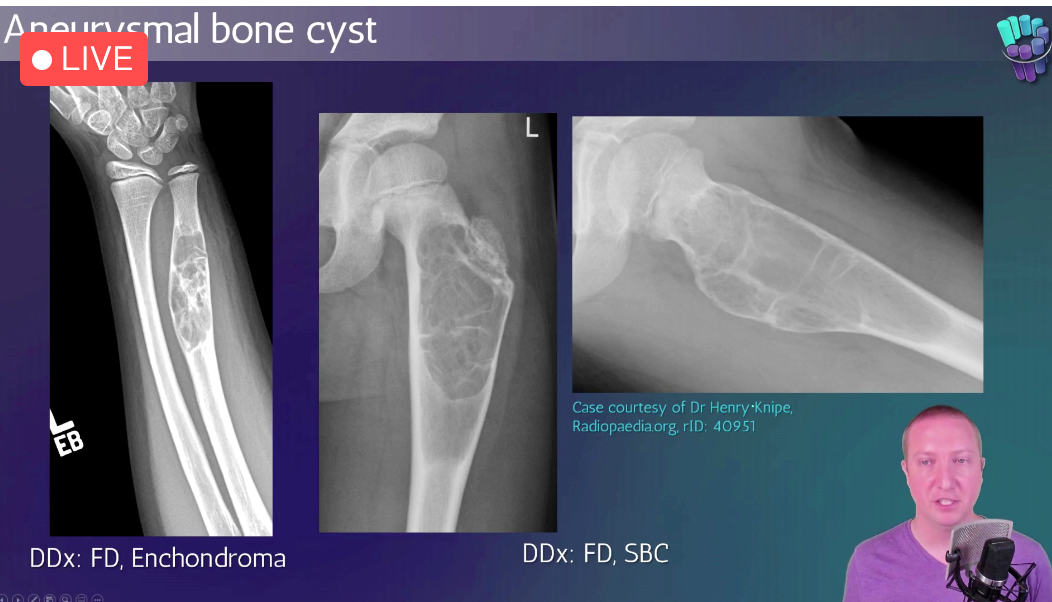

Aneurysmal Bone Cyst